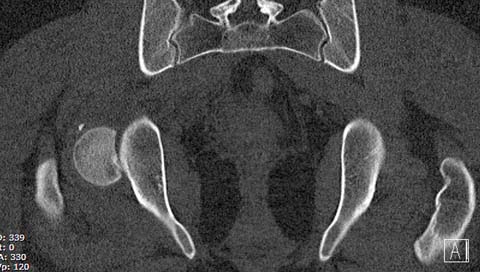

Здесь клинические примеры: Первый случай передний доступ, второй с ICP

monitor Flipp Trochanteris

и с переломом заднего края.